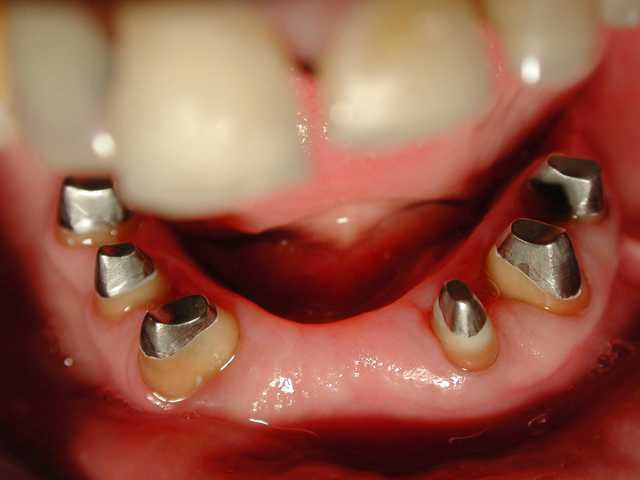

Voila un cas vite fait par un rentable: ramolli en 5 ans

Tu penses qu'on peut le rattraper en faisant inlay-core + bridge ?

Tu penses que j'ai perdu mon temps pour justifier des séances ?